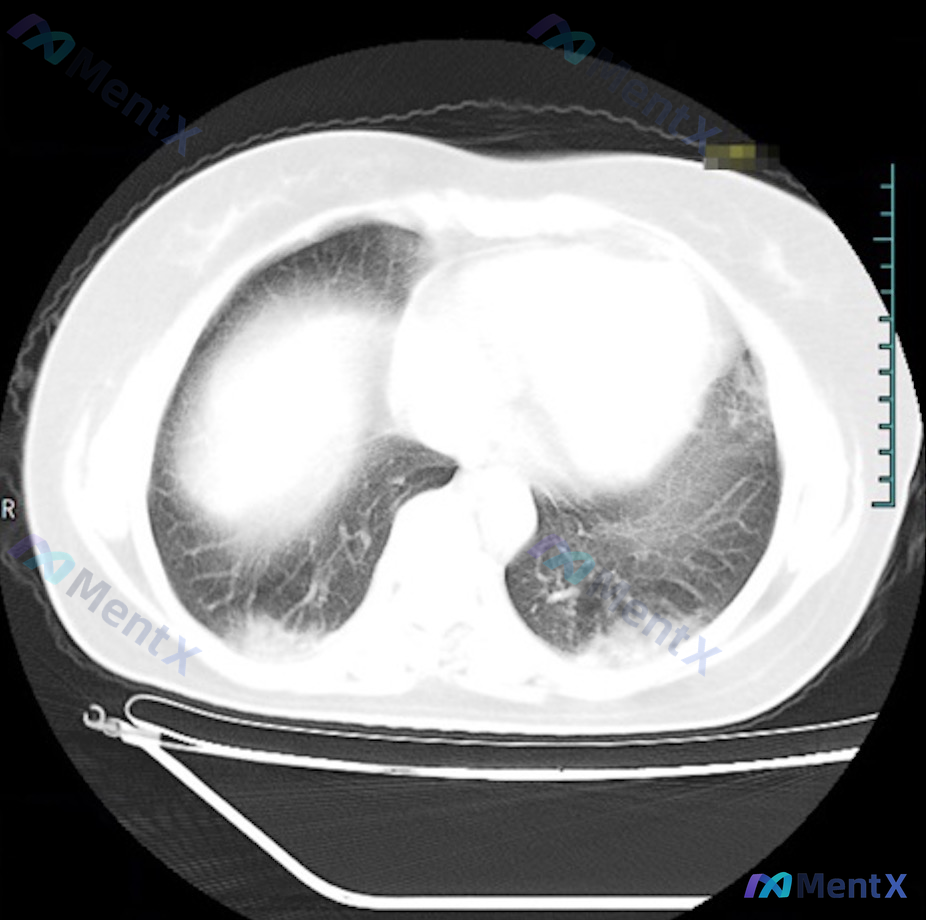

整理了一个挺有启发的病例,我们一起来看看: 基本情况 70岁患者,主要表现是逐渐出现的心力衰竭症状。 关键影像发现 拿到了三张片子:胸部MRI T2、心脏MRI电影和胸部CT。 1. 胸腔积液非常突出:右侧大量,右肺都受压萎陷了,左侧基本干净。 2. 心脏形态有点特别:心脏MRI电影轴位看,左室呈“...